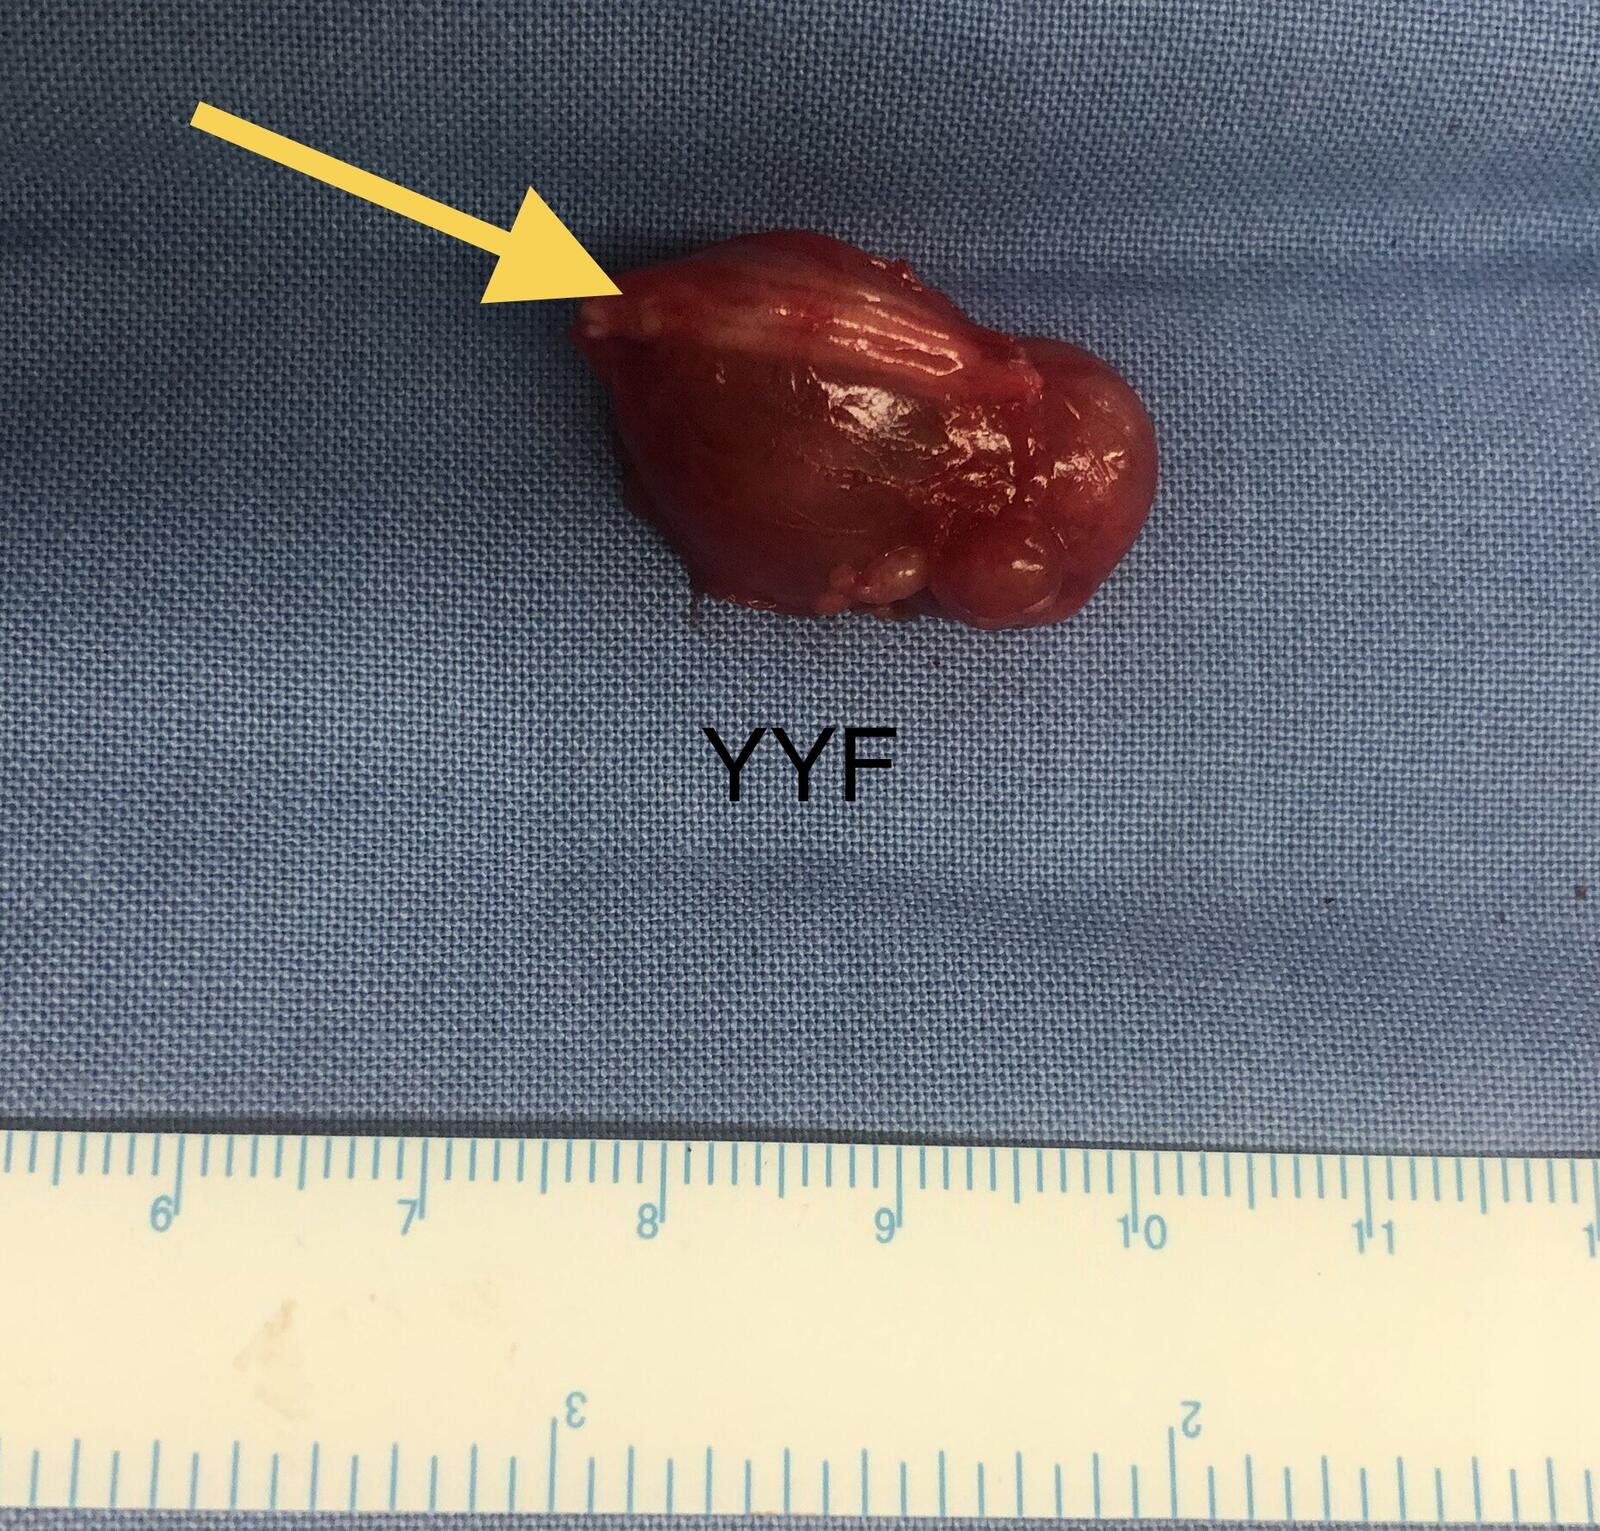

完整摘除是避免复发的唯一要素。

白色区域为病变起源的神经纤维

最终病理为神经纤维瘤,

其发病率远低于同为神经起源的神经鞘瘤。